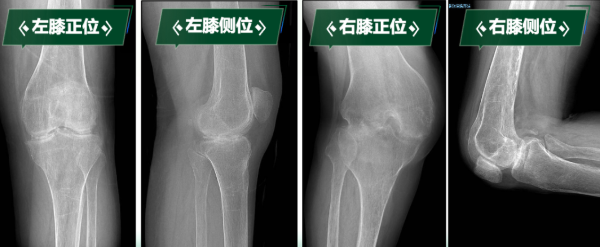

下肢處于功能“鎖死”狀態(tài)的劉阿姨,不僅被剝奪了行走能力,還導(dǎo)致嚴(yán)重肌肉萎縮、骨質(zhì)疏松,生活質(zhì)量急劇下降,手術(shù)是幫助她重新站起來的唯一途徑??剖腋叨戎匾?,經(jīng)多學(xué)科會診討論,制定周密治療規(guī)劃。曹曉瑞副主任醫(yī)師團(tuán)隊(duì)分析術(shù)前影像學(xué)資料,精確評估膝關(guān)節(jié)骨質(zhì)破壞、關(guān)節(jié)融合及周圍軟組織條件。

手術(shù)關(guān)鍵難點(diǎn)在于精準(zhǔn)截除融合骨組織、獲得屈伸間隙平衡、恢復(fù)下肢力線、確保韌帶平衡以重建膝關(guān)節(jié)功能。團(tuán)隊(duì)?wèi){借豐富經(jīng)驗(yàn)和嫻熟技術(shù),成功實(shí)施雙側(cè)人工全膝關(guān)節(jié)置換術(shù)。術(shù)后影像學(xué)檢查顯示,假體位置精準(zhǔn),下肢力線完美糾正,原本僵硬關(guān)節(jié)被活動自如的人工關(guān)節(jié)取代,患者功能恢復(fù)理想,能正常行走,生活質(zhì)量顯著改善。